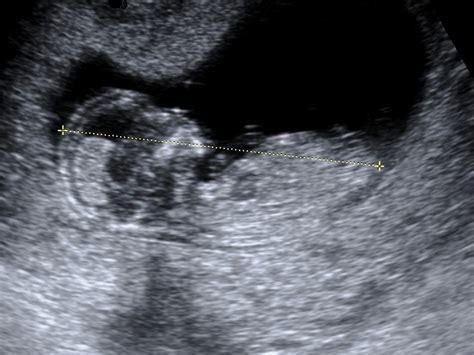

Obdobje med petim in dvanajstim tednom nosečnosti je zaznamovano z intenzivnim razvojem zarodka, ki se postopoma preobraža v plod. V tem času se oblikujejo vsi vitalni organi, kar imenujemo organogeneza. Srčno-žilni sistem se razvije, srčni utrip pa je na ultrazvočnem pregledu že viden. Ob koncu embrionalnega razvoja plod meri okoli 28 mm. V tem obdobju se pri nosečnici pogosto pojavijo utrujenost, slabost, ki lahko vključuje tudi bruhanje, ter spremembe v okusu in željah po hrani. Lahko se pojavi tudi glavobol, napihnjenost trebuščka pa je posledica upočasnjene prebave.

Plod v tem obdobju že meri okoli 12 cm (pri 16 tednih), do 20. tedna pa se začnejo meriti obsegi glavice, trebuha in dolžina stegnenice za oceno telesne teže, ki znaša okoli 300 gramov. Na ultrazvoku so lahko vidni že različni obrazni gibi ploda. Do 24. tedna teža ploda naraste na približno 650 gramov, koža se naguba, nalaga se podkožno maščevje, v pljučih pa se razvijajo pljučni mešički. Posteljica v 24. tednu tehta okoli 200 gramov.

V drugem trimesečju plod hitro raste. V 12. tednu meri okoli 5,4 cm in tehta 14 g, srce pa že deluje kot pri odraslem. Do 20. tedna plod meri približno 25 cm in tehta 300 g, na ultrazvoku pa so vidni že obrazni gibi. V 24. tednu plod tehta okoli 650 g, v 28. tednu pa že 1100 g, z razvitimi trepalnicami in nohti.

- Prvo trimesečje: Vključuje laboratorijske analize (krvna slika, krvni sladkor, krvna skupina, Rh faktor, testi na toksoplazmo in sifilis), ultrazvočno potrditev nosečnosti do 11. tedna ter pregled nuhalne svetline med 11. in 14. tednom, ki ocenjuje tveganje za kromosomske nepravilnosti.

- Drugo trimesečje: Običajno vključuje ultrazvočni pregled morfologije ploda v 20. tednu, ki podrobno oceni razvoj otroka. Potrebne so tudi analize krvne slike in urina ter test na nosečnostno sladkorno bolezen med 20. in 24. tednom.